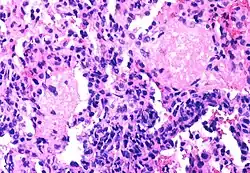

The spectrum of AIDS-related infections seen in different populations proves that AIDS is actually many diseases not caused by HIV

.jpg)

The diseases associated with AIDS, such as Pneumocystis jiroveci pneumonia (PCP) and Mycobacterium avium complex (MAC), are not caused by HIV, but rather result from the immunosuppression caused by HIV disease. As the immune system of an HIV-infected individual weakens, he or she becomes susceptible to the particular viral, fungal, and bacterial infections common in the community. For example, HIV-infected people in the Midwestern United States are much more likely than people in New York City to develop histoplasmosis, which is caused by a fungus. A person in Africa is exposed to pathogens different from individuals in an American city. Children may be exposed to different infectious agents compared to adults.[87]

HIV is the underlying cause of the condition named AIDS, but the additional conditions that may affect an AIDS patient are dependent upon the endemic pathogens to which the patient may be exposed.